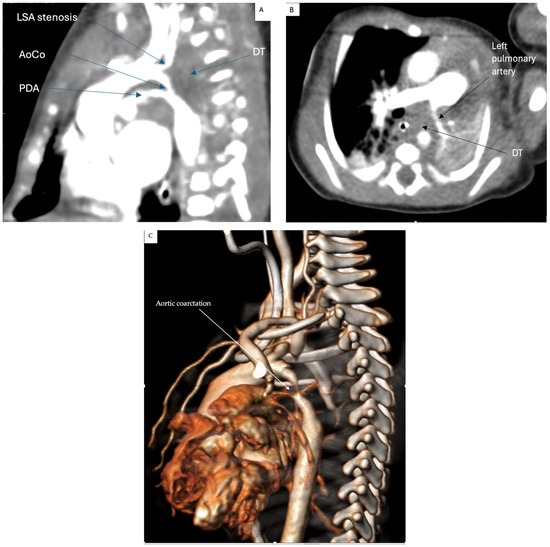

2. Case Presentation

2.1. Surgical Technique